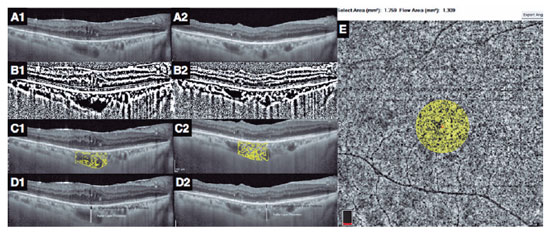

In each eye, the horizontal EDI-OCT scan passing through the fovea was selected for image analyses (Figure 1A1). Postoperatively, the EDI-OCT scan was matched to the one passing through the central foveal segment at baseline (Figure 1A2). The central choroidal thickness was determined as the distance between the lower boundary of the retinal pigment epithelium and the choroid-scleral interface(10). The CVI was computed as the ratio of the luminal area to the total choroidal area. The images were converted to 8 bits, and image thresholding adjustment was applied using ImageJ (version 1.47, National Health Institute, Bethesda, MA, USA) to highlight the vascular lumens (Figure 1B1 and B2). The choroidal area in OCT scans was binarized as reported in the literature(11). Then, each binarized image was converted to the RGB format, and luminal areas were highlighted using the color thresholding tool (Figure 1C1 and C2). The total choroidal, luminal, and stromal areas were calculated within the central 1500 µm. Bright pixels were defined as the choroidal interstitial area, whereas dark pixels were defined as the vascular luminal area(3,11).

The choroidal vascular layers were segmented manually. Measurements were performed by two graders, and the mean difference between their measurements was 4.4% ± 1.9% (range, 3%-8%). The Haller layer was delineated as the outer zone of choroidal vessels that were >100 µm(10). The H/C ratio was defined as the ratio of the Haller layer to the total choroidal thickness (Figure 1 D1 and D2)(4).

OCT-A measurements

The 6 × 6 mm OCT-A scans with a signal strength index ≥60 and without any motion artifact were used for analysis. OCT segmentation was automatically performed using the integrated module. The vascular densities of the inner and superficial capillary plexuses, CF, and central foveal thickness were measured using an integrated software. The CF was measured as the ratio of the flow area to the non-flow area in a 750 µm-radius circle, which was centered at the fovea (Figure 1 E)(4).

In the literature, choroidal thickness was the first parameter to be studied related to ERM, and studies have reported contradictory results(14-17). The present study did not disclose any significant change in the choroidal thickness in ERM. However, the baseline central choroidal thickness in ERM eyes tended to be thinner than that in the healthy fellow eyes and appeared to increase postoperatively. These minor changes in choroidal thickness may imply the initial displacement of the foveal center by the ERM away from the choroidal central point-where the choroid is thickest-and a postoperative return toward its original location. Another consequence of this tractional displacement is that postoperative OCT images do not pass through the exact same section of the choroid (Figure 1A1 and A2) because consecutive OCT images are matched to the retinal landmarks of the baseline OCT image.